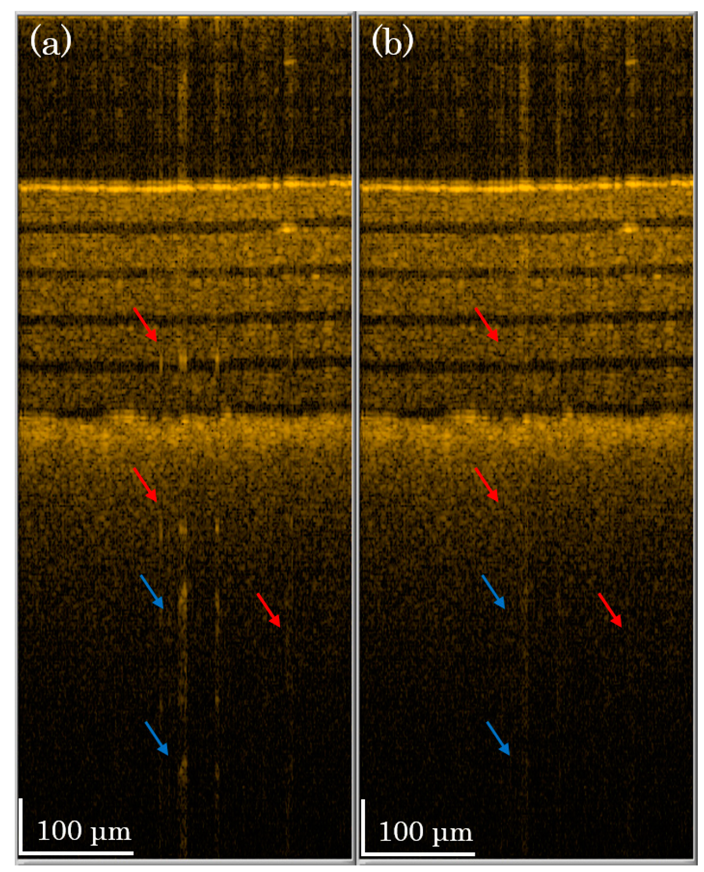

In Figure 5, we demonstrate the OCT image of the phantom sample of Figure 4. One B-mode scan image consists of 500 A-mode scans, and the A-mode scan shown in Figure 4 is the 250th line in Figure 5. In Figure 5a, we see many artifacts (indicated by arrows) in the image due to saturation problems. After performing our compensation method, shown in Figure 5b, most of the artifacts are suppressed (red arrows). One can see that some artifacts are not completely suppressed (blue arrows), because the assumption of linearity is not perfect. However, our method can significantly reduce the saturation artifacts.

To demonstrate the performance of our method on living tissue, we scan in vivo skin on a human finger. In Figure 6a, the saturation artifacts (indicated by arrows) are caused by strong scattering at the skin surface. The first two artifacts (red arrows) may disturb the image analysis. However, in Figure 6a, we see that the first two artifacts are suppressed with our method, and we see a clear tissue image. Though the last three artifacts (blue arrows) do not affect the tissue image, these artifacts are still well suppressed after our method is applied. Therefore, in Figure 5 and Figure 6, we demonstrate that our method can reduce saturation problems on not only phantom materials but also tissue in situ.